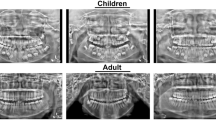

This paper reported a case of fusion between an impacted third molar and a supernumerary tooth, in which a surgical intervention was carried out, with the objective of removing the dental elements. The panoramic radiography was complemented by the Donovan's radiographic technique; but because of the proximity of the dental element to the mandibular ramus, it was not possible to have a final fusion diagnosis. Hence, the Cone‐Beam Computed Tomography—which provides precise three‐dimensional information—was used to determinate the fusion diagnosis and also to help in the surgical planning. In this case report we observed that the periapical, occlusal and panoramic were not able to show details which could only be examined through the cone‐beam computed tomography.